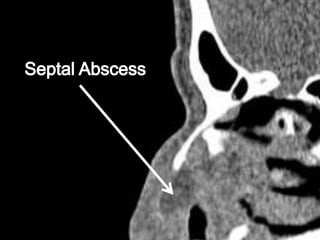

COMPLICATIONS OF SEPTAL

HEMATOMA

• #6 Blood under perichondrium separates avascular cartilage from blood supply, resulting in necrosis in 3 days. Abscesses may form 6-7 days out from injury. Dangerous complications include osteomyelitis, orbital/intracranial abscess, meningitis, and cavernous sinus thrombosis